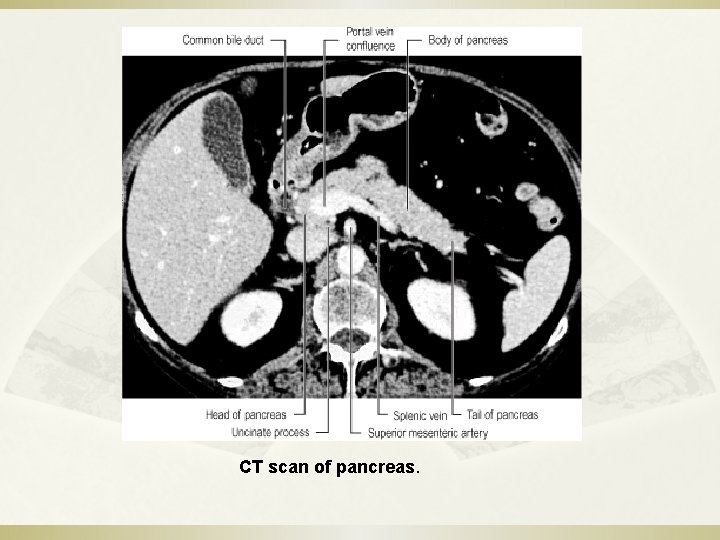

CT scan of pancreas.